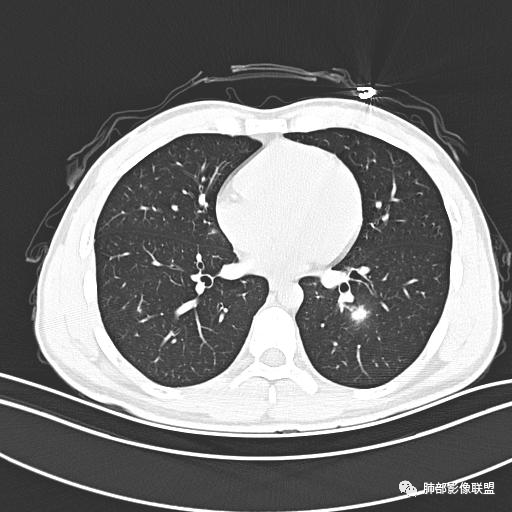

男,19岁

主  诉:发热、全身皮疹2天。

现病史:患者源于2天前受凉后出现发热,最高体温为38.5℃,且颜面部出现少量皮疹,无鼻塞、流涕、咳嗽、咳痰,未在意而未作特殊处理,次日全身皮疹逐渐增多至全身,伴轻度瘙痒,在当地卫生所给予抗病毒、抗感染治疗(具体用药不详)体温有所下降,但皮疹无明显消退,无腹痛、头痛,食欲无明显减退,为进一步诊治,遂于今日急来我院求治,患者目前精神尚可,体力正常,食欲正常,睡眠正常,体重无明显变化,大便正常,排尿正常。

小强:青年,发热,皮疹;双肺散在结节,周围磨玻璃,点晕征,疱疹病毒感染,鉴别荚膜组织胞浆菌,结核。 大雄:青年,急性起病,发热伴全身皮疹2天,抗病毒治疗体温有下降。双肺随机分布大小不等类圆结节,“点晕征”。考虑水痘-疱疹病毒(VZV)血播询问接触史,查体皮疹分布以及形态基本可诊断。 王开金江津中心医院呼吸科:青年男性,起病急,病程短,以发热,皮疹为首发症状,感染指标以单核细胞升高为主,胸部ct双肺多发结界,周围有晕,点晕表现,随机分布,同意於老师意见,水痘疱疹病毒血流感染累及肺。 王秀仙:双肺多发大小不等结节,周围有晕,边缘模糊,呈点晕征表现。青年,急性起病,发热伴全身皮疹2天,抗病毒治疗体温有下降。考虑疱疹病毒。鉴别荚膜组织胞浆菌。 傅昌瑜:19岁男性,发热、全身皮疹2天,单核细胞增高,双肺多发结节,结节边缘见边界不清磨玻璃影。点晕征+发热、全身皮疹+单核细胞增高——考虑水痘-带状疱疹病毒肺炎。 一切∮随缘:年轻男性,发热,皮疹两天,实验室,CRP,PCT增高,影像:双肺多发散在磨玻璃结节,边界欠清,大小不等,呈点晕征改变,以血管束周围分布为主,局部血管束略增粗,其它无明显改变,考虑:1:病毒性肺炎(水痘疱疹病毒?不知道皮肤有无改变)2:真菌(组织胞浆菌,血管侵袭性肺曲霉)3:GPA4:寄生虫(实验室没有看到嗜酸细胞增高) 赵山河:双肺散在结节,周围有晕,边缘模糊,呈点晕征表现。青年,急性起病,发热伴全身皮疹2天,抗病毒治疗体温有下降。考虑水痘—疱疹病毒感染。洪桥爱:青年男性,发热、皮疹2天,伴瘙痒,皮疹于面部首发,之后进展至全身,虽然没有对皮疹进行描述,但是从出疹时间及皮疹进展情况,伴瘙痒,应该就是个水痘患者;CT提示双肺随机分布结节影,部分结节伴有边界不清晕征,考虑水痘血播肺。 刘强:年轻男性,急性起病,皮疹,发热,抗感染治疗体温下降,说明有效。影像表现为散在点晕征,感染类疾病谱(疱疹病毒,真菌,结核),结合年龄,皮肤皮疹,考虑水痘-疱疹病毒性肺炎。 小兜:男性,19岁,发热皮疹两天,颜面部至全身,CRP,降钙素及单核增高。CT示双肺散在小结节,周围伴磨玻璃影,点晕征,考虑为水痘-带状疱疹病毒(varicella-zoster virus,VZV)肺炎 必有路:青年,皮疹+发热+“点晕征”→水痘-疱疹病毒(VZV) 许慧良:青年男性患者,发热、皮疹2天,体温最高38.5℃,第3天皮疹扩展至全身,伴瘙痒,胸部CT:双肺多发随机分布的小结节,结节周边见边界模糊的晕征,考虑水痘病毒感染流心明智:男,19,急性起病,发热伴全身皮疹2天。出疹顺序头→全身,抗病毒有效。胸部CT:两肺多发大小不等类圆形实性小结节影,随机分布,结节周围环绕GGO,边界模糊,呈点晕征。出疹特点是关键,未提示。考虑:血播病毒性肺炎,水痘-疱疹病毒?麻疹?鉴别荚膜组织胞浆菌、TB、血管炎、寄生虫等。 浪迹天涯:病灶多为5-10mm大小结节,结节周围可见磨玻璃样的晕环,常多发,可分布于肺内任何区域,考虑水痘—带状疱疹病肺炎如果短时间内有新的一个区域浸润,更加能说明,